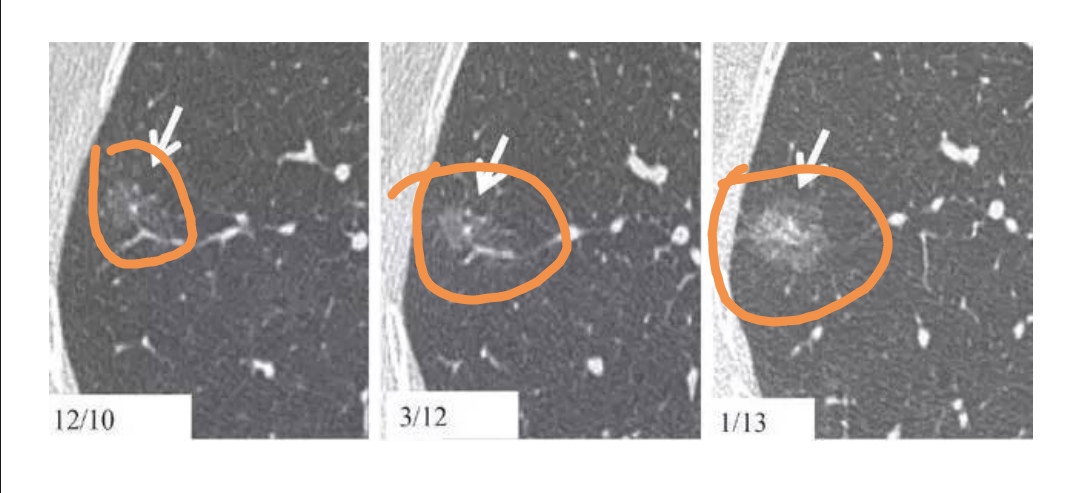

相隔1年,磨玻璃结节变成实性结节,为恶性